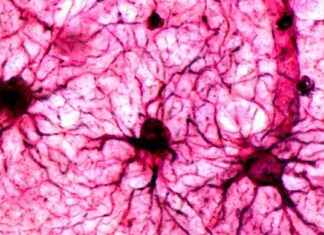

Comment les souvenirs effrayants sont stockés dans le cerveau

Une nouvelle compréhension de nos souvenirs se dessine grâce à l'étude des astrocytes, des cellules en forme d'étoile présentes dans le cerveau. Longtemps considérées comme des supports nourriciers, ces cellules garderaient – comme les neurones –...